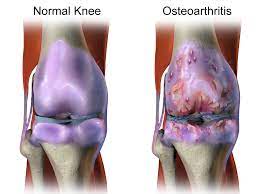

관절염 원인

- 노화: 나이가 들면서 관절에 부담이 가해져서 관절염이 발생할 수 있어요.

- 손상 및 부상: 관절에 손상이나 부상을 입으면 염증이 발생해 관절염이 생길 수 있어요.

- 유전적 요인: 가족 중에 관절염 환자가 있거나, 유전적인 요인으로 인해 관절염이 발생할 수 있어요.

- 자가면역 질환: 루푸스, 레이노드 현상, 류머티즘 관절염 등과 같은 자가면역 질환은 몸의 면역 체계가 관절을 공격하여 관절염을 발생시킬 수 있어요.

- 감염: 세균, 바이러스, 균류 등이 관절에 감염을 일으키면 관절염이 발생할 수 있어요.

관절염 증상

- 통증: 관절 염증으로 인해 생기는 가장 대표적인 증상입니다. 활동하면서 또는 휴식할 때도 통증이 있을 수 있어요.

- 관절 부어오름: 관절이 부어오르거나 따뜻해지는 증상이 있을 수 있어요.

- 관절 강직: 오랫동안 움직이지 않거나 아침에 일어날 때 관절이 뻣뻣하게 느껴지는 것을 말해요.

- 팽만 및 충혈: 관절 주위의 피부가 붉어지거나 붓는 증상이 있을 수 있어요.

- 움직임 제한: 관절 통증 및 염증으로 인해 움직임이 제한되거나 유연성이 떨어질 수 있어요.

- 딸림 현상: 관절에 뼈가 부딪히거나 문제가 생기면 소리가 나거나 불안한 느낌이 들 수 있어요.